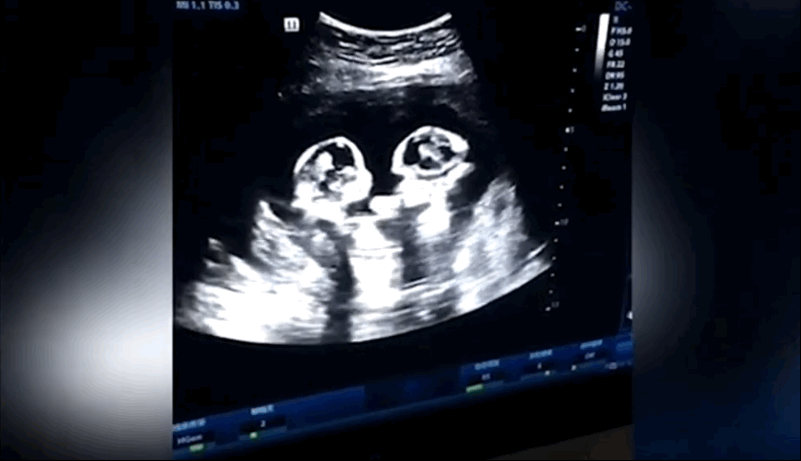

Lo que vemos: la ecografía de una mujer embarazada de cuatro meses donde se aprecia a dos gemelas que aparentemente se están golpeando entre sí dentro del útero de la madre. Las pequeñas compartían saco amniótico y placenta. Sucede una vez cada 60.000 de casos. El clip de ultrasonido muestra que las pequeñas se encuentran…